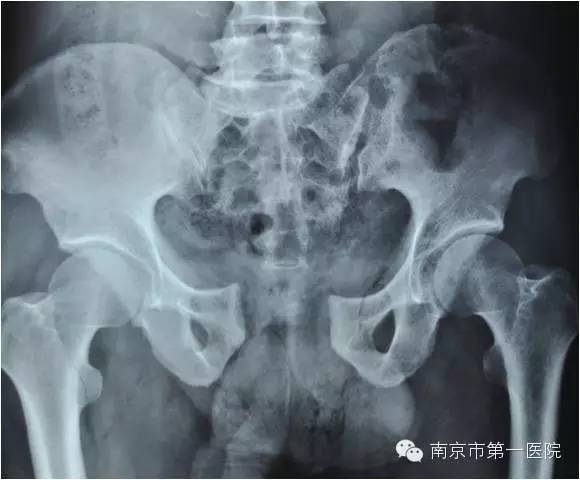

随后,老张第一时间被送到当地医院进行了简单处理,处理完又立刻转到南京市第一医院进行进一步抢救。据了解,小卡车大约1.5吨重,受伤的部位在骨盆,由于受到碾压和挤压,导致骨盆内的肌肉撕裂、血管损伤,骨盆也粉碎性骨折。另外,同时存在右侧胫腓骨粉碎性骨折及大面积软组织损伤。

据了解,骨盆骨折是一种严重外伤,占骨折总数的1%~3%,多由高能外伤所致,半数以上伴有合并症或多发伤,致残率高达50%~60%。因此,在对患者进行输血、补液、液体服务等抗休克治疗的基础上,ICU立即组织院内骨科专家进行会诊。